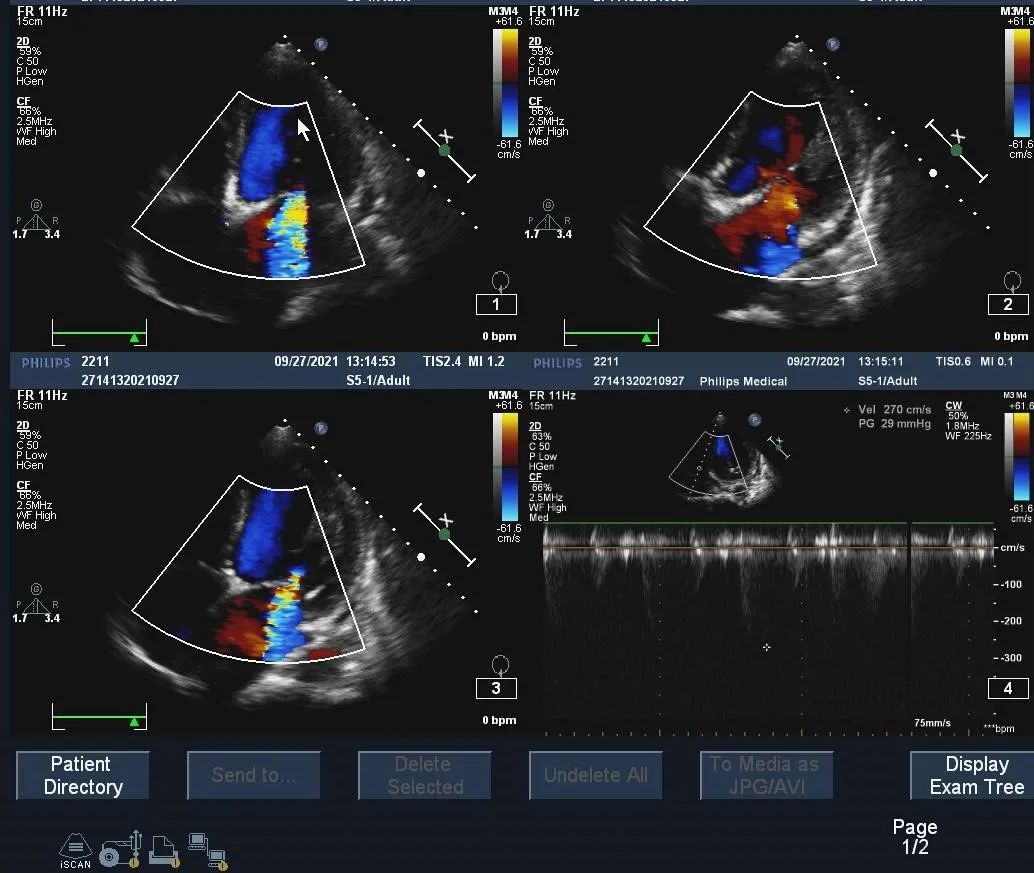

超声心动图所见:

1.全心增大,以左室增大为明显,左室呈球形。左室壁厚度偏薄(平均约6mm),室壁收缩运动普遍减弱。

2.主动脉瓣叶及结构显示不清,瓣膜明显增厚钙化,似呈纵裂式二叶瓣,开放明显受限,过瓣流速428cm/s,最大压差73mmHg,关闭欠佳,二尖瓣瓣环增宽,大量返流。余瓣膜形态及运动未见异常

3.升主动脉、肺动脉稍增宽

4.EF:29%